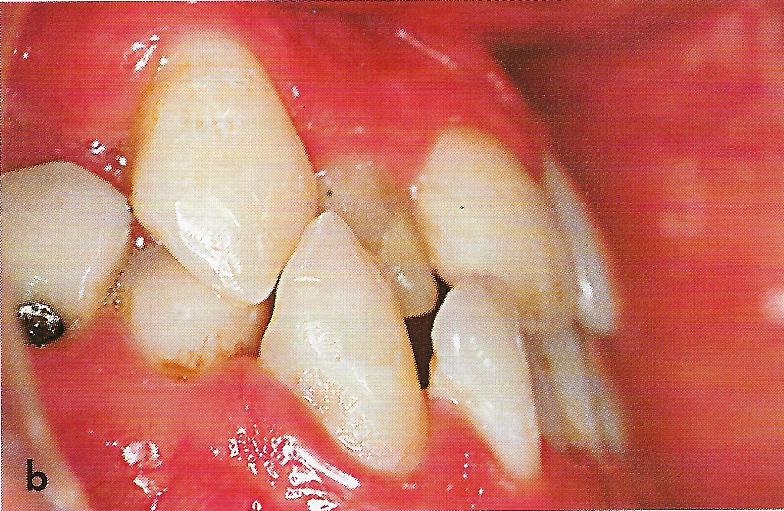

Bei der therapeutischen Ankylosierung werden zunächst die entsprechenden Milchzähne extrahiert. Da eine Ankylosierung durch eine Zerstörung des Parodontiums ausgelöst wird, muß das Desmodont mit einer Kürette entfernt werden. Obwohl unsere Patientin erst 7 Jahre alt war, konnten nach der Extraktion an beiden Milcheckzähnen, besonders an Zahn 63, bereits apikale Resorptionen festgestellt werden. Um die Zähne später sicher und vollständig replantieren zu können, mußten deshalb mehr als die üblichen 2 mm der Wurzelspitze entfernt werden. Anschließend wurden die Wurzelkanäle konventionell aufbereitet und mit einem Calciumhydoxidpräparat gefüllt (Abb. 7). Nach Entfernung des Koagulums wurden die Zähne vorsichtig replantiert und mit einem vorbereiteten Draht an den benachbarten Zähnen stabilisiert (Abb. 8). Auf den Milchmolaren wurden Aufbisse angebracht, damit die Milcheckzähne ohne störende Okklusions- und Artikulationskontakte einheilen konnten.

Der Schienungsdraht wurde 4 Wochen nach dem Eingriff entfernt (Abb. 9). 8 Wochen nach der Replantation waren die Milcheckzähne absolut immobil und ergaben einen hellen Kopfschall bei Perkussion, so daß von einer Ankylosierung ausgegangen werden konnte.